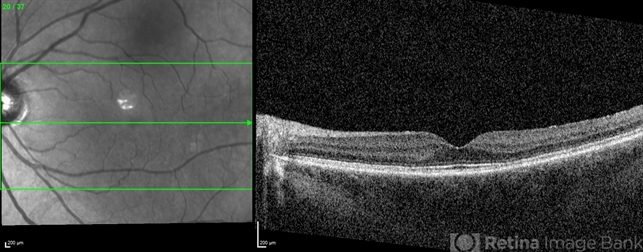

- plaquenil toxicity, OCT

- 58 year old woman with 11 year history of plaquenil use with early parafoveal outer retinal attenuation and bull's eye on near-infrared imaging. Left eye